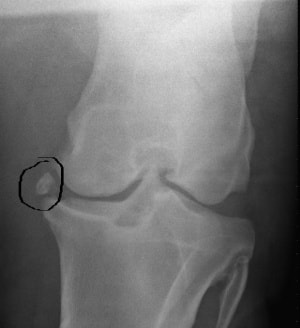

Jei žirgas nešlubuoja, deja, tai dar nereiškia, kad jo kojos sveikos. „Nelygus“ bėgimas, po pertraukos užstingę sąnariai, tinstančios kojos, netaisyklinga stovėsena ir kiti panašūs simptomai gali reikšti rimtus pažeidimus. Laimei, kojų problemoms diagnozuoti yra puiki, tik nepelnytai ignoruojama priemonė – rentgenas. Nepasikliaukite vien savo akimis – jos šioje situacijoje bevertės. Žirgai yra talentingi skausmo ir problemų maskuotojai. Jie gali apgauti net ir žymiai labiau patyrusius specialistus. Patikėkite, ne vienam veterinarijos gydytojui teko išgyventi didžiulę nuostabą, pamačius žvalaus ir „beveik nešlubo“ žirgo kojų vaizdą rentgeno nuotraukoje, atskleidusioje gilias, su judėjimu beveik nesuderinamas problemas.

Taigi, jei planuojate žirgą joti, būtinai padarykite kojų nuotraukas - be jų nežinosite realios padėties ir negalėsite suplanuoti teisingo krūvio.

Antkaulis – dėl kaulą dengiančios plėvelės (antkaulio) pažeidimo prasidėjęs nekontroliuojamas jos augimas, o vėlesnėse stadijose ir sukaulėjimas. Priežastys – tiesioginis sumušimas, ilgalaikis raiščių/sausgyslių prisitvirtinimo vietų perkrovimas. Jei antkaulis neliečia sausgyslės, nervų ar raiščių, galite jį laikyti kosmetiniu defektu. Jei liečia – žirgas nuolat šlubuos. Antkaulį galima bandyti tirpdyti vaistais, bet jokių garantijų, kad sulauksite sėkmingo rezultato. O ir pats gydymas bus ilgas ir žirgui nemalonus. Be to, nėra jokių garantijų, kad „senas" antkaulis vėl nepradės augti.

Sąnario paviršių gali pažeisti neteisinga mityba ir neadekvatūs krūviai, tiesioginiai sąnario pažeidimai, per greitas augimas jaunystėje. Dažniausios problemos (osteochondrozė, osteochondritas): sąnarinio paviršiaus nusitrynimas, kremzlės pažeidimai ir atplyšimai, sąnarinės kapsulės ir raiščių sukaulėjimai, tokių sukaulėjimų atlūžimas ir patekimas į sąnario vidų („čipai“, kurie mechaniškai drasko glotnų sąnario paviršių ir blokuoja judėjimą, sukeldami stiprų skausmą bei uždegimą). Juos galima apgydyti stipriais vaistais ir ilgalaikiais papildais, kurie gana kenksmingi žirgo skrandžiui. O tam tikrais atvejais padės tik operacija. Gydymo kurso kaina nemaža, didelė ir problemos atsinaujinimo tikimybė. Jei sąnaryje jau yra atplyšusių dalelių („čipų“), vienintelė išeitis - operacija. Gera naujiena, kad jos jau atliekamos Lietuvoje, bloga naujiena - toks gydymo kompleksas tikrai kainuos daugiau nei kainavo jūsų žirgas.

Kojų gydymo „kaina“: rentgeno nuotrauka - apie 40 Lt. Visų kojų ištyrimui gali prireikti iki 16-18 nuotraukų, nes probleminę vietą gali tekti apžiūrėti keliais skirtingais kampais. Gydymo arba skausmo mažinimo kaina gali siekti nuo kelių šimtų iki kelių tūkstančių litų.